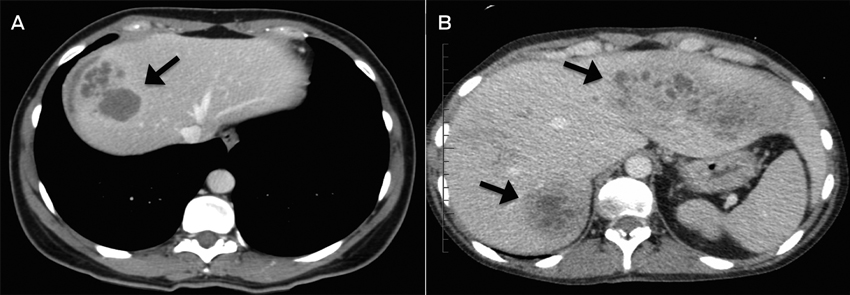

A: Case 3; CT image showing multiloculated hepatic lesions (arrow), central cystic changes and necrosis. B: Case 2; CT image showing irregular lesions (arrows) through both left and right hepatic lobes.

Radiological findings are often non-specific for fascioliasis. Ultrasonography and CT images often show poorly circumscribed lesions during the liver parenchymal phase.3